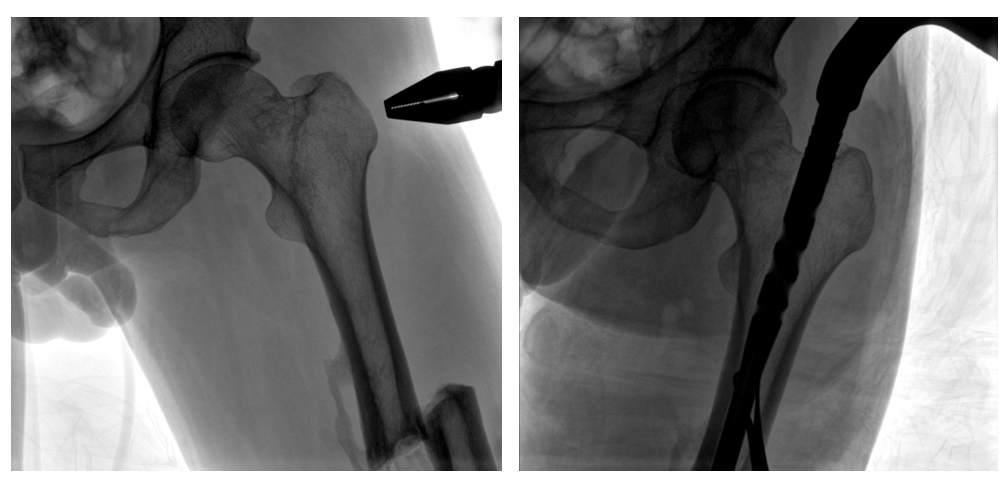

病例二:

患者左股骨干完全骨折,經(jīng)過醫(yī)生評估,使用“髓內釘內固定術”進行治療。髓內釘內固定術需要將入釘點至骨折部位的影像完全展示,在一些長骨的骨折中,對視野范圍要求高。

一體式C形臂釘點至骨折部位的臨床影像

在進行髓內釘內固定術時,醫(yī)生需要同時觀察到入釘點和骨折部位的情況,PLX119C大平板一體式C形臂能夠呈現(xiàn)更廣闊的成像面積,滿足大部分長骨髓內釘內固定術的攝片需求。